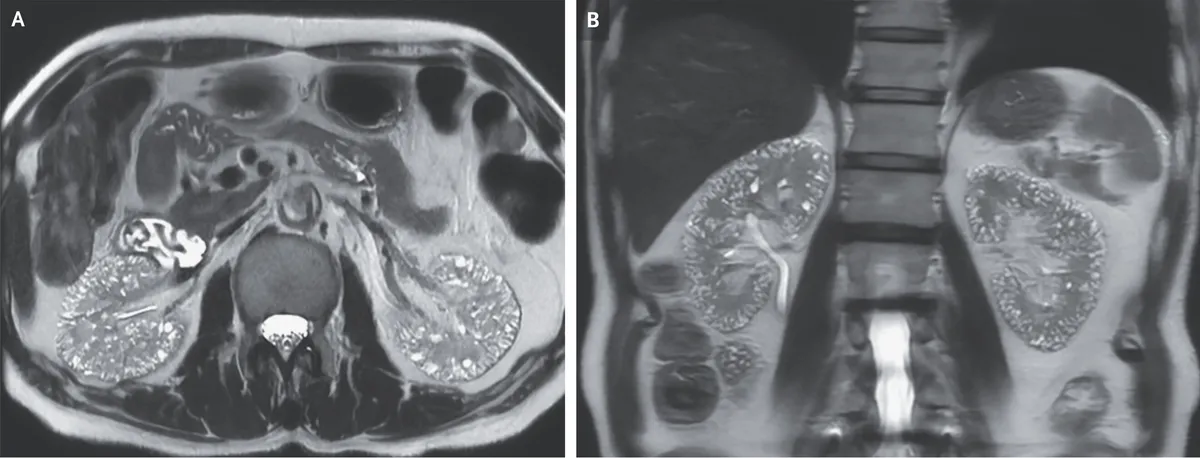

O paciente negava qualquer histórico familiar de doença renal cística. A RM ponderada em T2 revelou numerosas microcistos localizados no córtex e na medula de ambos os rins (Imagem abaixo - Painel A, corte axial; Painel B, corte coronal).

Foi feito o diagnóstico de microcistos compatíveis com nefropatia induzida por lítio. O uso de lítio está associado a diversos efeitos nefrotóxicos, incluindo diabetes insipidus nefrogênico, acidose tubular renal e nefropatia túbulo-intersticial crônica.